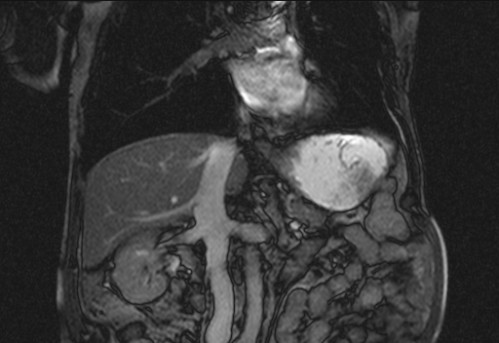

Auffälliges Abdomen bei der Vorsorgeuntersuchung einer älteren Dame

ICD: C64

68 Jahre alte Frau. Sie geht zur Darmspiegelung im Rahmen ihrer Krebsvorsorgeuntersuchung. Der Internist bemerkt bei der ergänzenden sonografischen Untersuchung des Abdomens einen auffälligen Befund.